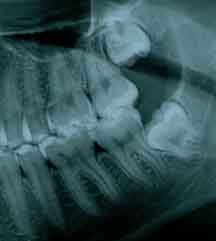

ASPECTO DE SISO INCLUSO:

Para saber se a pessoa vai ter ou não os dentes do siso e se eles vão causar algum problema, é necessário um exame radiográfico.

A radiografia panorâmica ou tomografia são os mais utilizados. Além de mostrar a presença ou não dos mesmos, mostram sua relação com os órgãos vizinhos, tais como dentes, nervo alveolar inferior e cavidade sinusal.